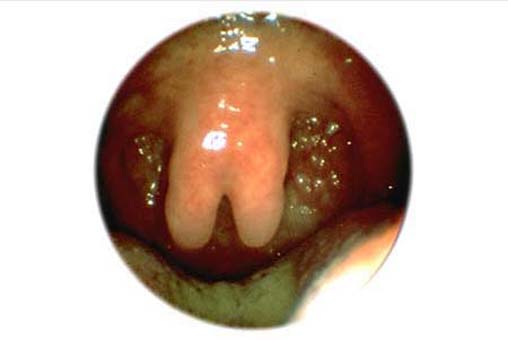

Uvula bifida ........ Zum Kapitel